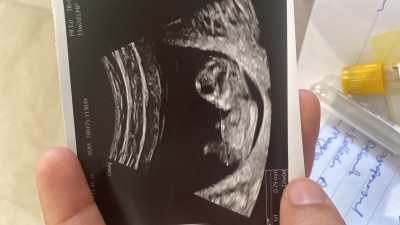

Cinsiyet tahmini alabilir miyim çok heyecanlıyım😍😍

Gebelik haftası 12

Erkeğe benzettim ben

Yapay zeka erkeğe benziyor dedi canm

Kafası büyük ondan erkek diyorum:)

Kıza benziyor

Kıza benzettim 😍